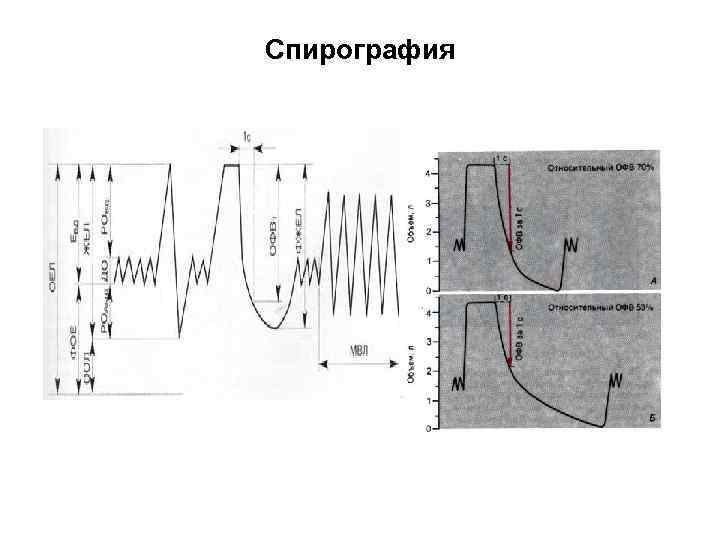

Инструментальные исследования. Исследование функции внешнего дыхания – Спирография – характерные признаки нарушения бронхиальной проходимости: снижение ФЖЕЛ и ОФВ 1, снижение соотношения ОФВ 1/ФЖЕЛ. При частых обострениях и развитии эмфиземы легких снижается ЖЕЛ. Пробы с использованием бронходилятаторов – необходимы для уточнения степени обратимости бронхиальной обструкции/

Спирография